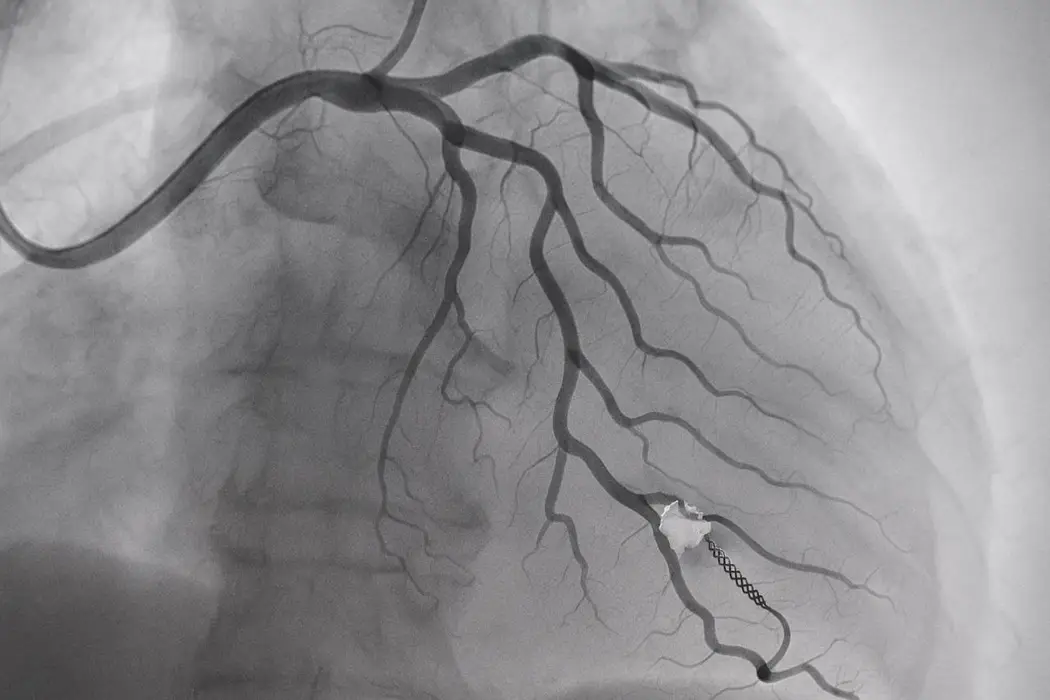

مقدمة رأب الوعاء (Angioplasty) هو إجراء طبي يستخدم لعلاج انسداد الشرايين واستعادة تدفق الدم الطبيعي إلى القلب أو أجزاء أخرى من الجسم. يعتبر هذا الإجراء طفرة في عالم طب القلب والأوعية الدموية، حيث يوفر بديلاً أقل تدخلاً مقارنة بالجراحات التقليدية. في هذا المقال، سنتناول تفاصيل إجراء رأب الوعاء، فوائده، مخاطره، والتقنيات الحديثة المرتبطة به. ما هو رأب الوعاء؟ رأب الوعاء هو إجراء غير جراحي يتم باستخدام قسطرة بالونية صغيرة تُدخل […]